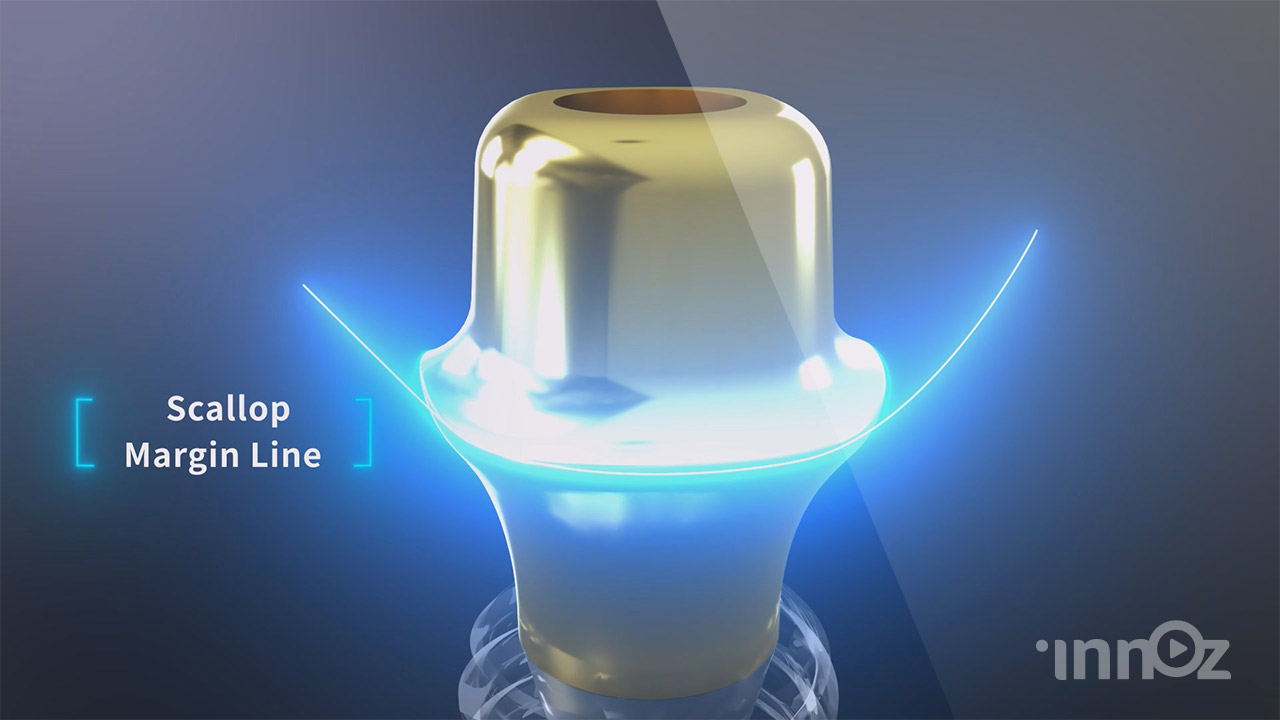

오스템임플란트

치과의료기기 전문기업

치과의료기기 전문기업

치과의료기기 전문기업